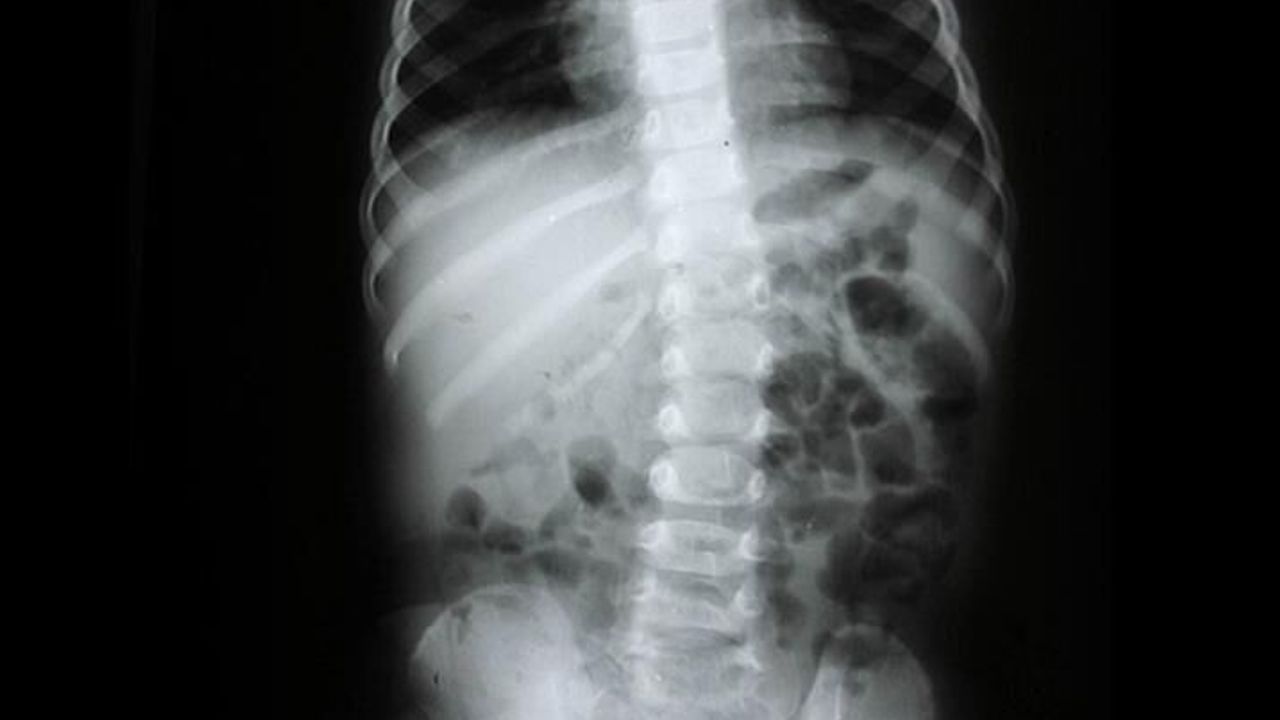

Omurilik sinirleri, beyinden vücuda sinyalleri taşıyan sinirlerdir. Omurilik sinirleri zarar görürse, vücuttaki ilgili bölgelerde duyu kaybı, hareket kaybı, refleks kaybı ve diğer sorunlar ortaya çıkabilir. Omurilik sinirlerinin zarar görmesi, genellikle bir travma sonucu olur. Omurga yaralanmaları, omurilik sinirlerinin en yaygın zarar görme nedenlerinden biridir. Omurga yaralanmaları, trafik kazaları, düşmeler, spor yaralanmaları ve şiddet olayları gibi durumlarda meydana gelebilir. Omurilik sinirlerinin zarar görmesi, enfeksiyonlar, tümörler ve bazı genetik hastalıklar nedeniyle de ortaya çıkabilir.